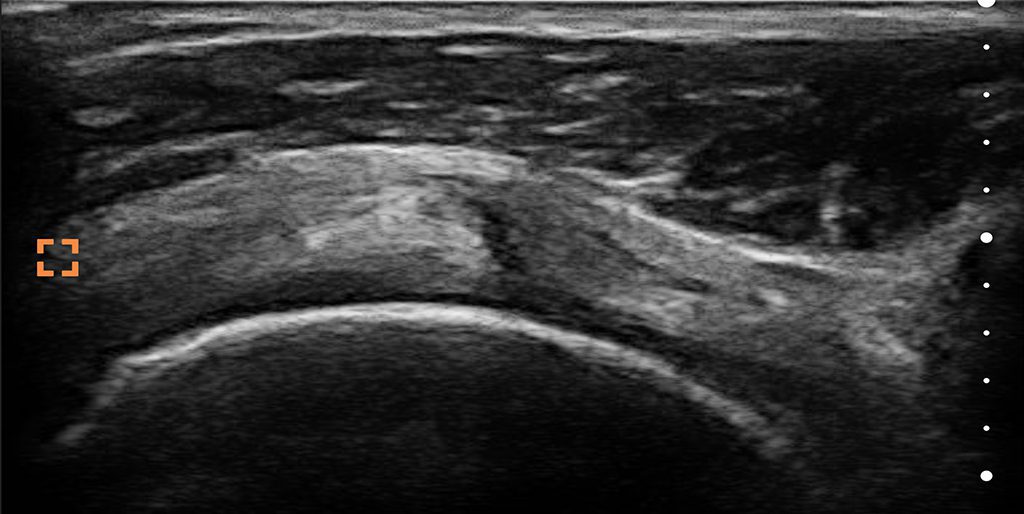

Échographie rendue compréhensible.

Mode-T™ enseigne pendant que vous scannez. Voyez instantanément l'anatomie étiquetée, pour que même les utilisateurs novices puissent interpréter les images et prendre des décisions en toute confiance.

Accélérez l'Apprentissage

Les structures anatomiques clés sont automatiquement mises en évidence et étiquetées pour réduire le temps d'interprétation.